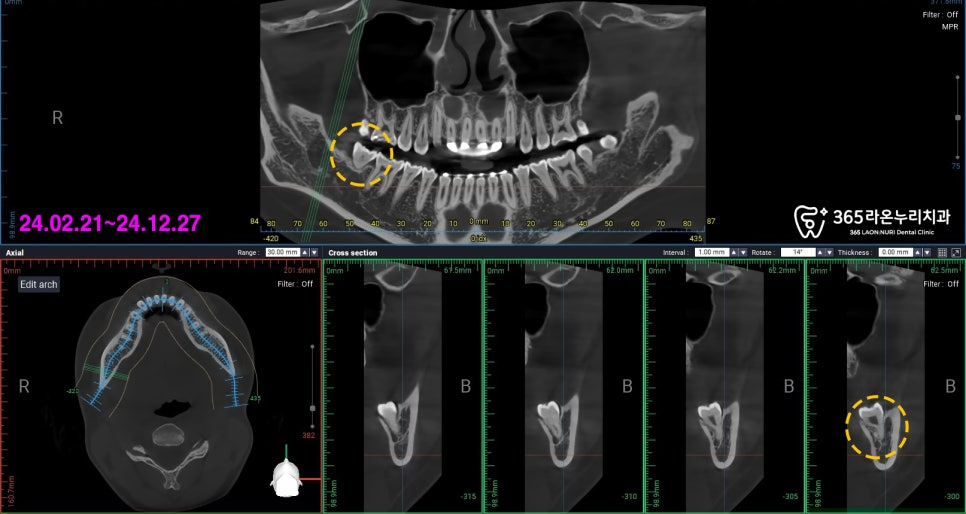

그래서 3차원 정밀을 촬영하여

사랑니 및 하치조 신경의 위치 파악 및

발치 계획을 세웠는데요.

그리고 나서, CT 사진을 보시면

사랑니 뿌리 끝과 하치조 신경이

닿아 있는 것을 확인할 수 있습니다.

이렇게 치아 뿌리와 긴밀하게 닿아 있다면

주변 구조물에 손상을 일으키지 않게 뽑아야 되므로

그만큼 사랑니 발치가 까다로워집니다.

그러나 동탄동 치과 에서는

대표 원장의 숙련된 임상 기술로

하치조 신경의 손상 없이,

무사히 사랑니 발치를 진행해드렸는데요.